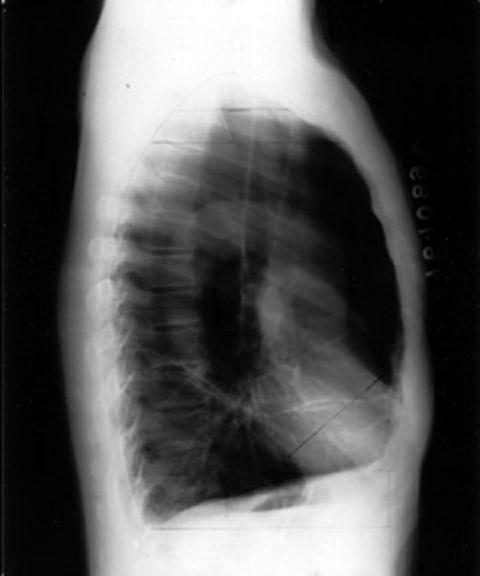

• Hyperlucent lung fields

• AP diameter increased

• Flat diaphragms

• Multiple blebs

• Retrosternal and infracardiac air

• Radiologic TLC